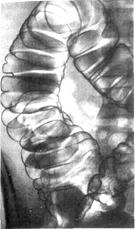

Рис. 3022708710. Картина толстой кишки после подкожного введения пилокарпина. Выраженная глубокая гаустрация. Спазмы. Укорочение поперечноободочной кишки. Ваготония.[44]

Рис. 3022708715. Картина толстой кишки после подкожного введения атропина. Широкая толстая кишка; удлинение и свисание вниз поперечноободочной кишки. Гаустры выражены слабо (паралич блуждающего нерва). [45]

В норме рельеф слизистой оболочки кишки изменчив. [55] При пероральном заполнении толстой кишки гаустры распределены относительно равномерно, имеют гладкие закругленные очертания. Распределение, глубина и форма гаустр изменяются в связи с перемещениями кишечного содержимого и движениями кишечной стенки.

При ирригоскопии гаустрация менее глубокая, а местами незаметна.

На внутренней поверхности кишки гаустрам соответствуют полулунные складки слизистой оболочки.